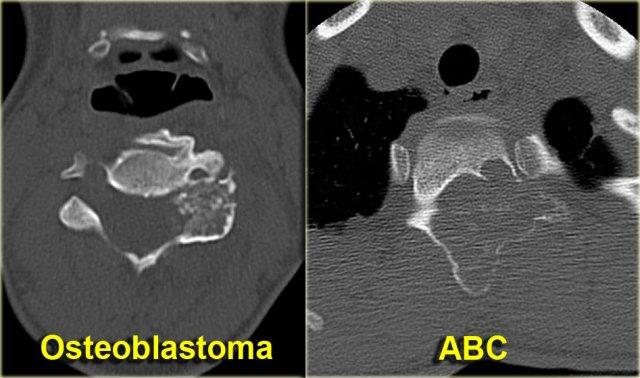

Osteoblastoma

U tạo xương (Osteoblastoma) là một khối u lành tính đơn độc hiếm gặp, tạo ra chất dạng xương và xương.

Cần xem xét u tạo xương khi nang xương phình mạch (ABC) nằm trong chẩn đoán phân biệt của tổn thương cột sống (hình).

U tạo xương điển hình có kích thước lớn hơn 2 cm, ngoài ra hoàn toàn giống với u xương dạng xương (osteoid osteoma).

Discriminator:

- Mention when ABC is mentioned.

Aneurysmal Bone Cyst

ABC (Nang xương phình mạch) là tổn thương xương tiêu xương đơn độc, dạng phồng, giới hạn rõ, chứa đầy máu.

Được gọi là phình mạch vì có đặc tính phồng to.

ABC được cho là kết quả của một quá trình phản ứng thứ phát sau chấn thương hoặc tăng áp lực tĩnh mạch.

Đôi khi có thể tìm thấy tổn thương nền như u tế bào khổng lồ (GCT), u tạo xương (osteoblastoma) hoặc u nguyên bào sụn (chondroblastoma).

ABC có thể xảy ra ở hầu hết mọi vị trí trong hệ xương.

Discriminators:

- Must be under age 30.

- Must be expansile